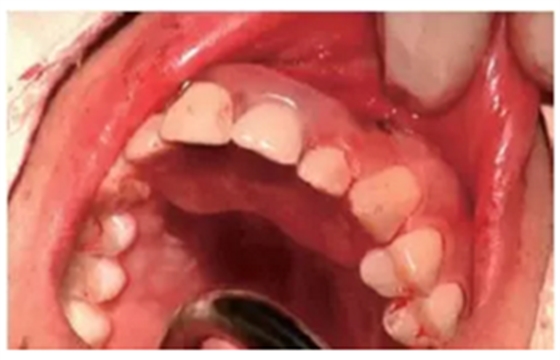

種植后修復(fù)

戴上套筒冠基臺進(jìn)行即刻修復(fù)。注意不是所有植入的種植體都可以進(jìn)行即刻修復(fù),醫(yī)師可以通過扭力值并結(jié)合ISQ松動度測量值來選擇修復(fù)的種植體。

圖18 進(jìn)行即刻修復(fù):a.戴上基臺;b.在基臺上戴入套筒冠;c. 套筒冠固位到原有義齒上;d.患者戴上有套筒冠的覆蓋義齒;e. 即刻修復(fù)完成后曲面體層片